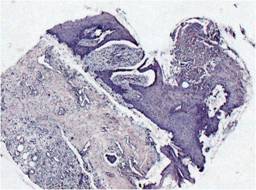

Al quinto día se descubrió el injerto (Figura 1), se recolectó muestra para cultivo de la superficie, se midió el área de injerto clínicamente adherida calculando el porcentaje de injerto exitoso. Se tomó biopsia tangencial de la zona injertada de 0.5 x 0.5 cm que incluye dermis y epidermis, se colocaron en formol y se enviaron al departamento de patología.

Figura 1: Fotografías tomadas al quinto día de la colocación del injerto, mismo paciente. (A) Brazo derecho control con aplicación de placebo. (B) Brazo izquierdo con aplicación de PRPAA. Se observa en la imagen del lado izquierdo sufrimiento en los bordes con pérdida posterior de esa zona y sangrado abundante al momento del retiro del material que recubre el sitio, por el contrario en el lado derecho existe un sangrado y formación de hematoma mínimo sin pérdida de injerto.